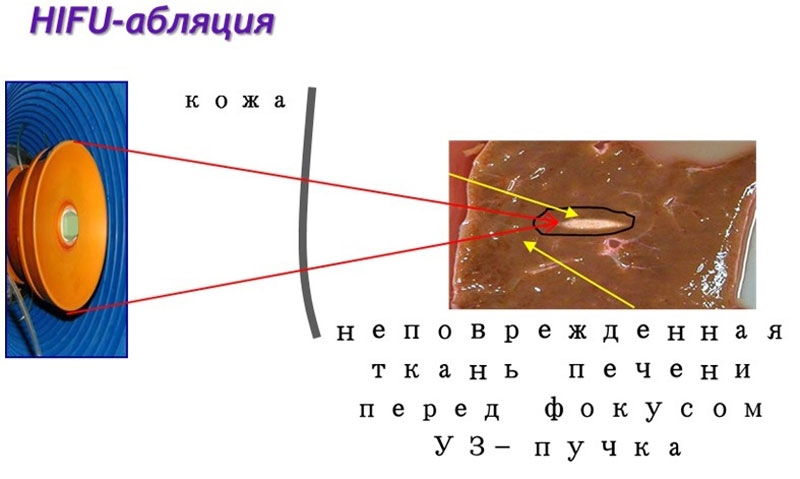

В Центре впервые внедрена неинвазивная технология дистанционной ультразвуковой абляции опухолей паренхиматозных органов HIFU

Проведены первые операции при миоме матки, опухолях печени, поджелудочной железы, надпочечников и др.